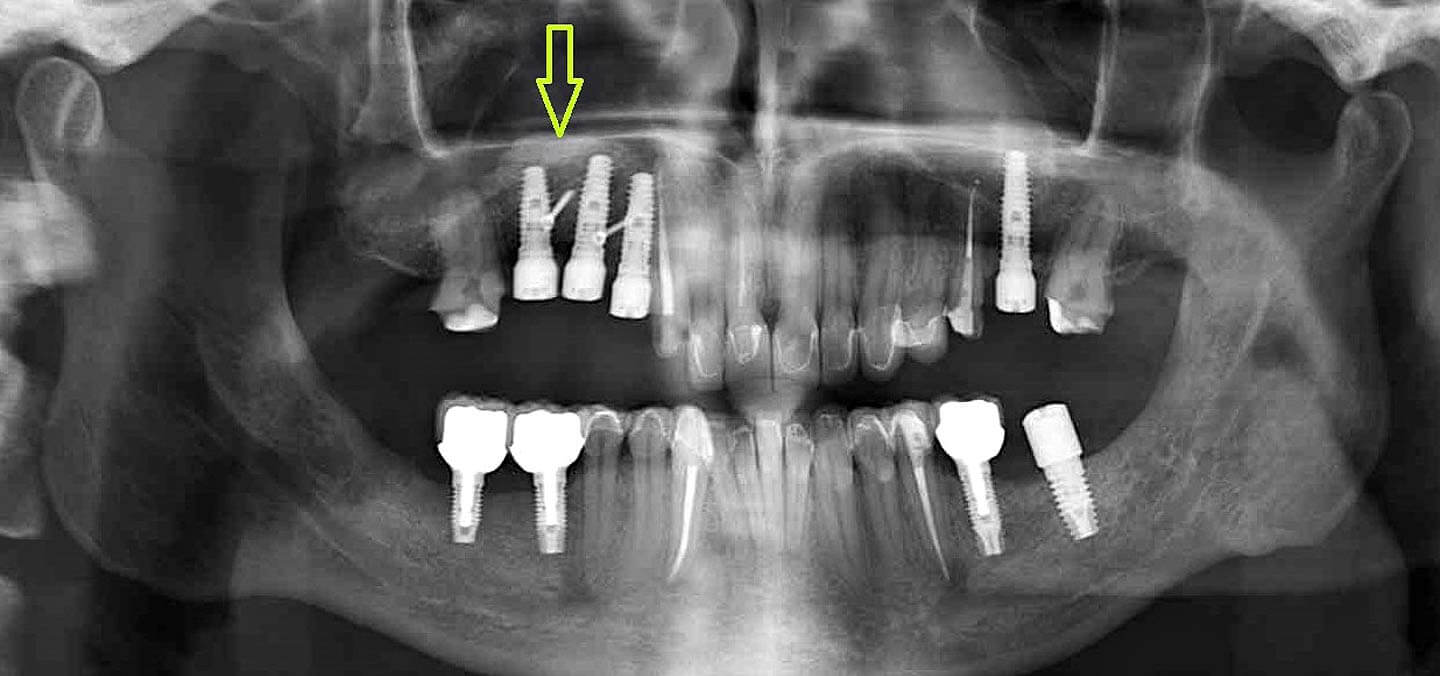

Исследование на рентгене после имплантации зубов

Раздел: Снимки-откровения